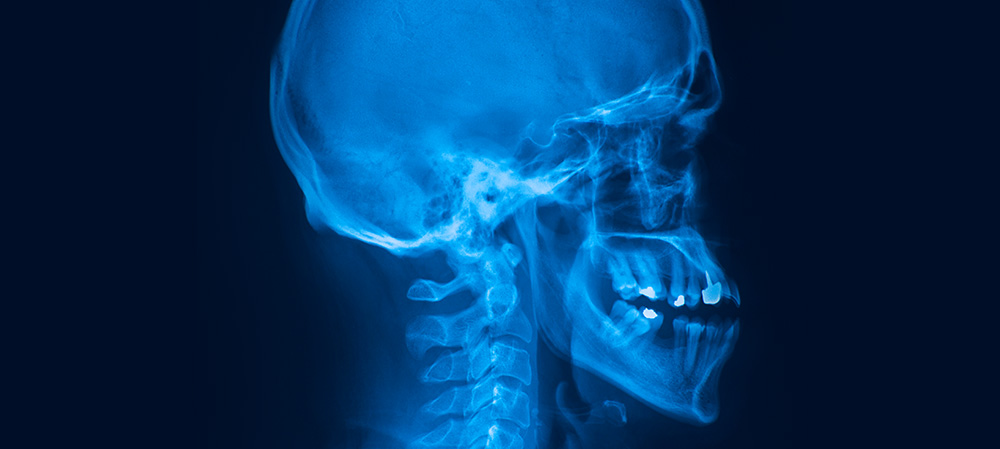

Provádíme veškerá RTG vyšetření kostí, páteře, lebky, plic a břicha včetně speciálních projekcí. RTG snímky jsou pořizovány v digitální formě na systému FUJI.

Veškerá RTG vyšetření provádíme bez objednání. Snímky pořízené od 8.00 do 12.00 popisujeme ihned, odpolední pak druhý den.